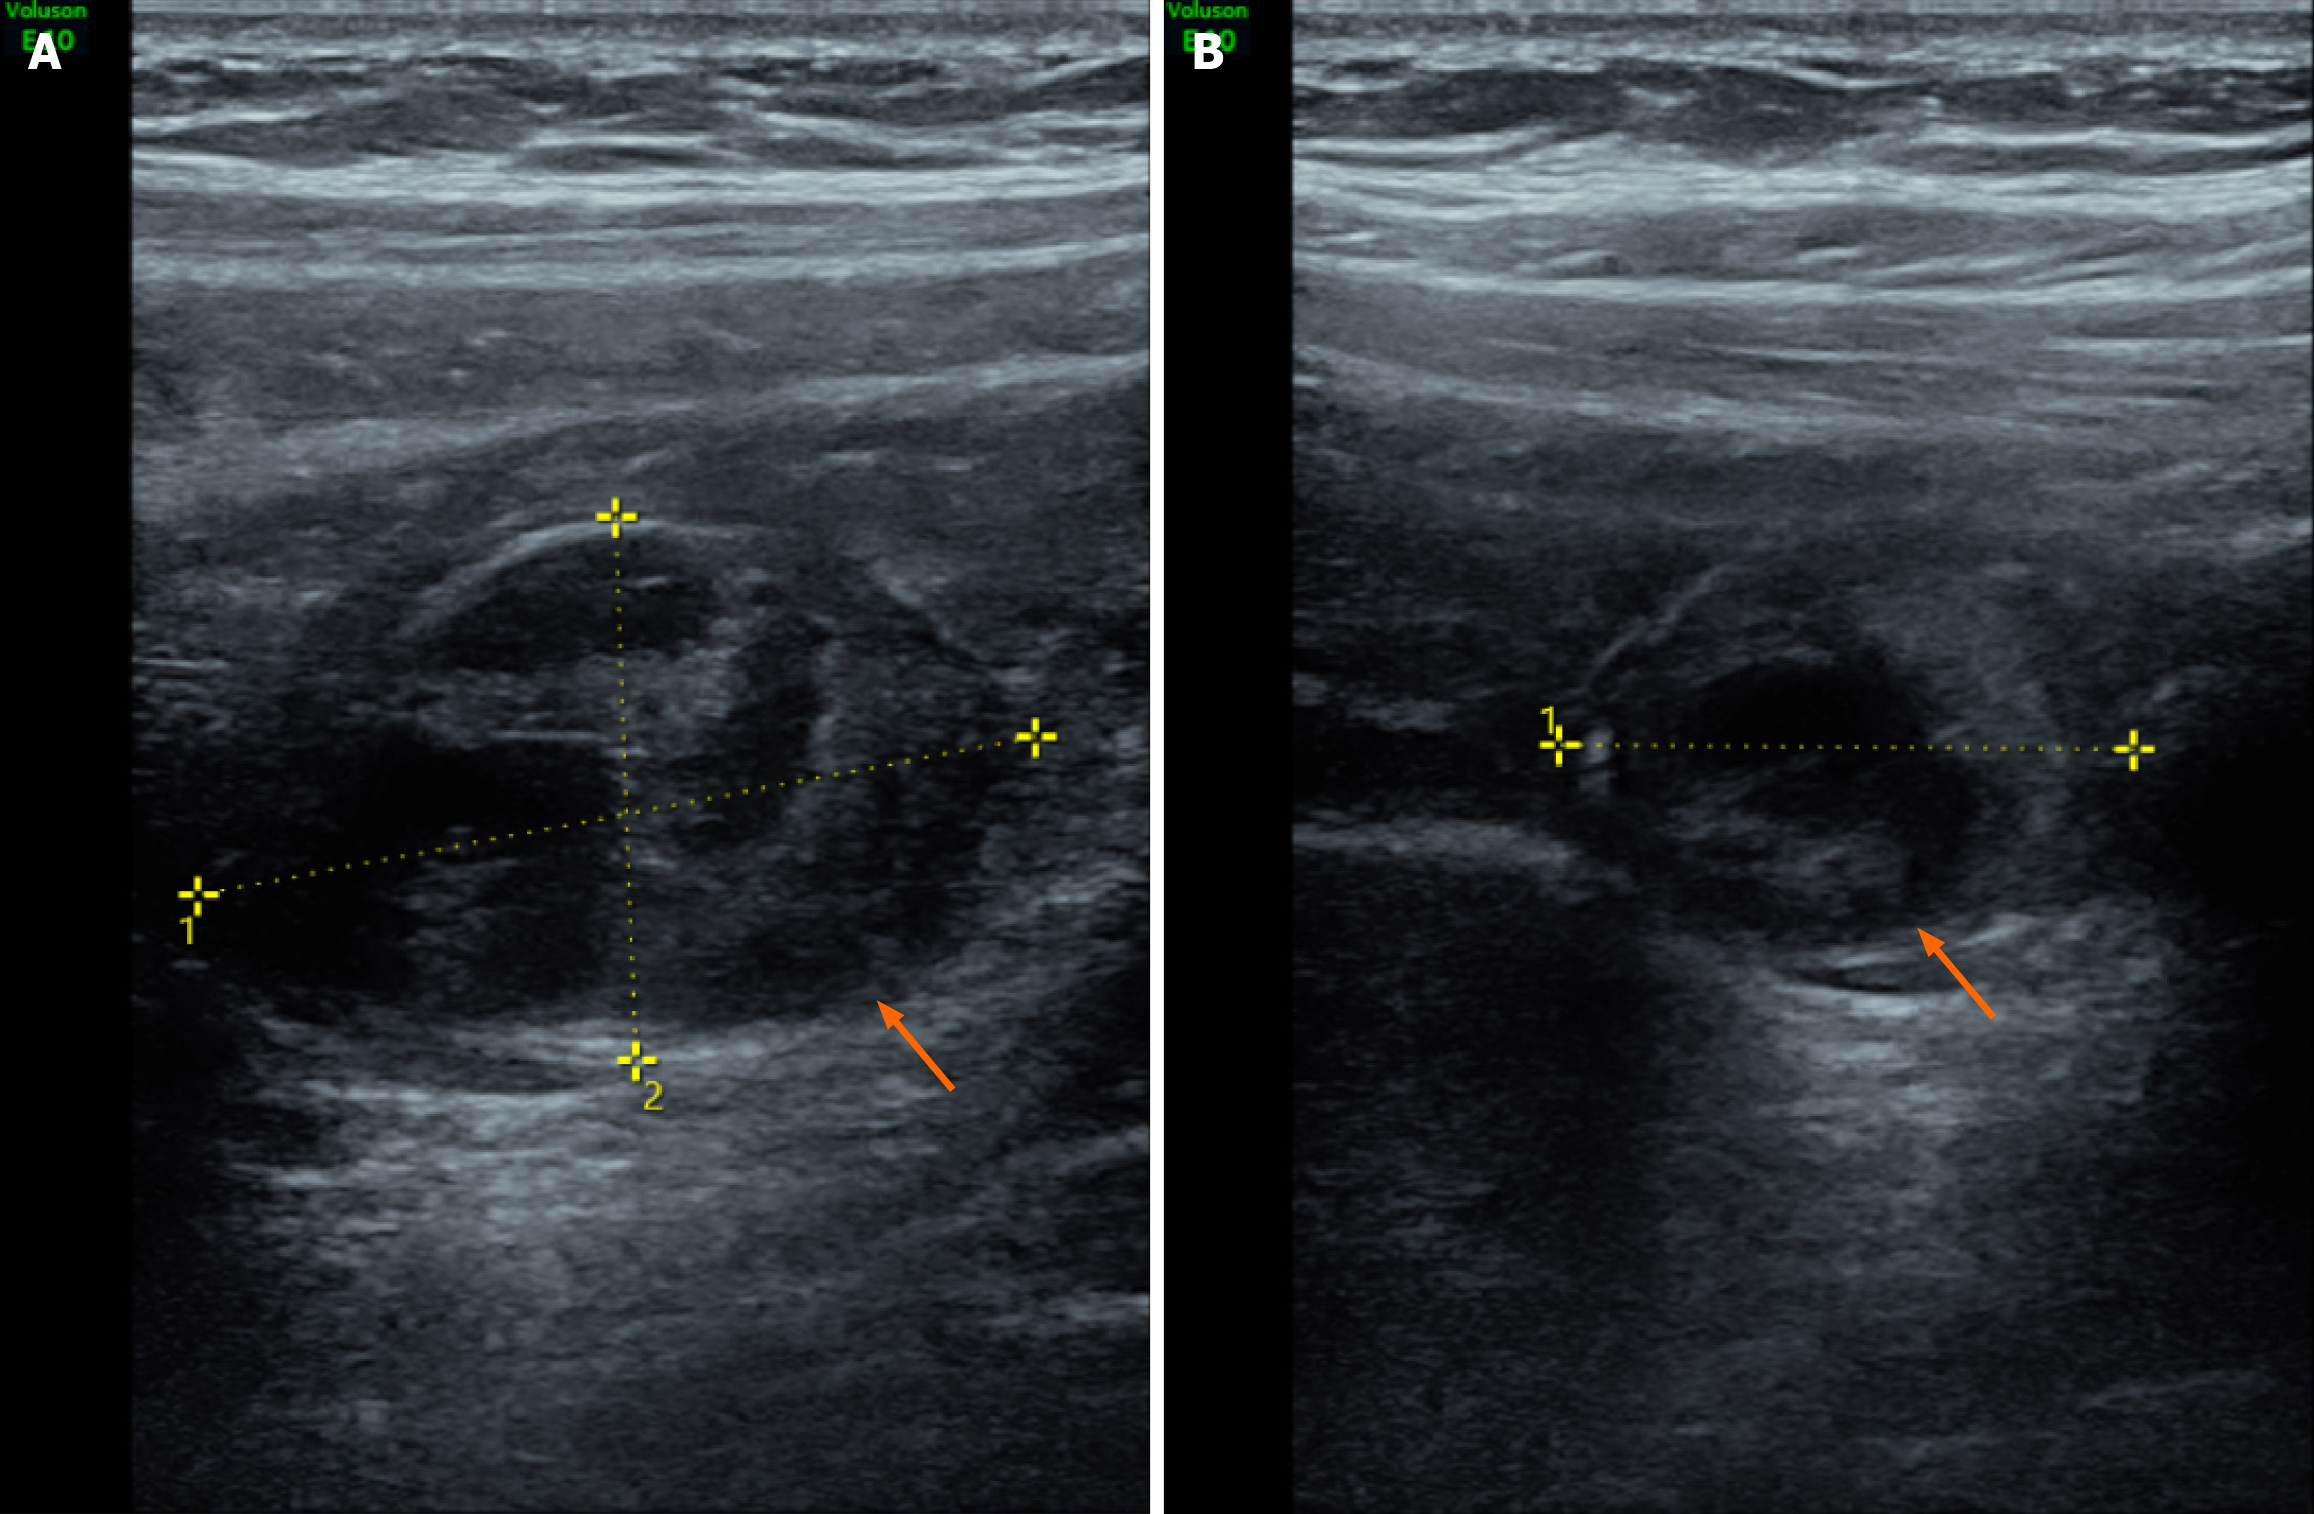

MRI of a 28-year-old pregnant woman with surgically and pathologically confirmed unruptured tubal ectopic pregnancy (Figure 1). Axial T2-weighted fat-suppressed image shows a small nodular hyperintense focus (arrow) within the gestational sac. Axial T1-weighted image demonstrates the nodule with isointense signal relative to muscle. Diffusion-weighted image (b-value = 800 s/mm²) shows no restricted diffusion within the lesion. The coronal magnetic resonance image of the entire abdomen shows that the gestational sac is located between the lower edge of the right lobe of the liver and the right iliac fossa. Coronal T2-weighted image confirms uterine morphology consistent with a left unicornuate uterus and a right rudimentary horn. The uterus is deviated toward the left pelvic sidewall. Axial contrast-enhanced T1-weighted fat-suppressed image reveals vivid enhancement of the nodule and mild enhancement of the cyst wall. Targeted transabdominal ultrasound, performed with MRI guidance, identifies the ectopic gestational sac in the right upper abdomen, within the subhepatic region (Figure 2). Intraoperative and histopathological correlation (Figure 3). Laparoscopic view showing a left unicornuate uterus and normal left ovary within the pelvic cavity. Intraoperative photograph shows the ectopic fallopian tube and ovary (arrow) displaced to the right upper abdomen, firmly adherent to the inferior hepatic surface and capsule.

Tubal ectopic pregnancy within an undescended right fallopian tube, associated with a left unicornuate uterus and a contralateral rudimentary horn.